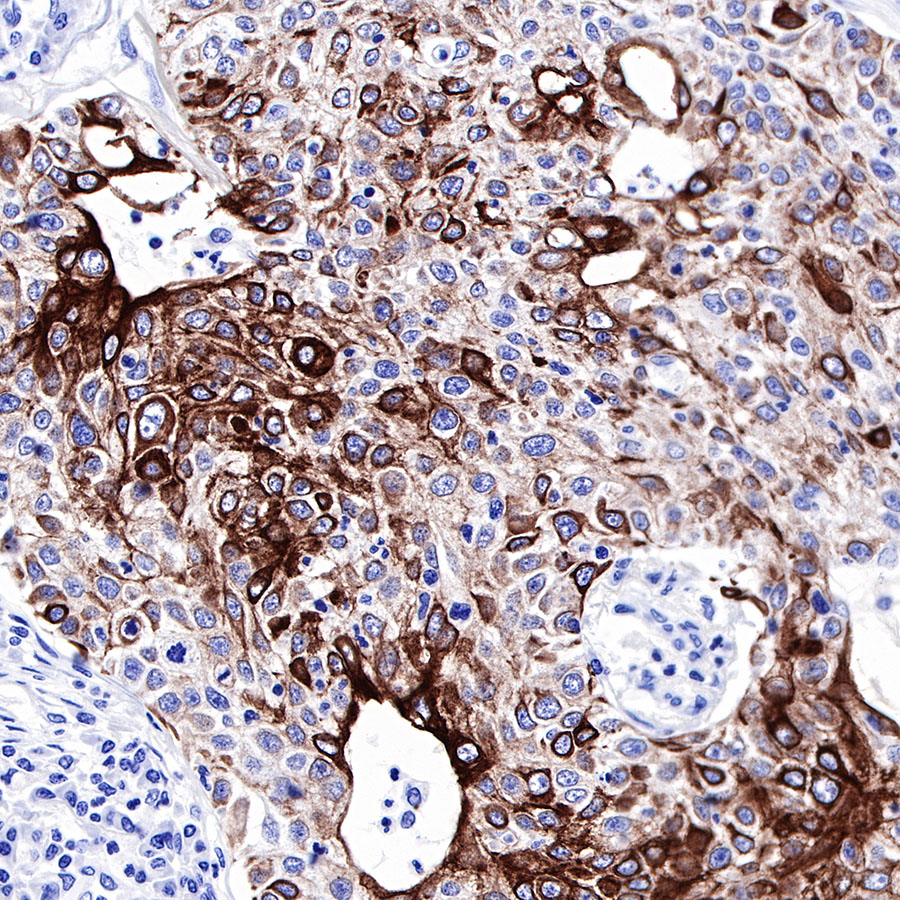

Background

| IHC-P |

1:500-1:2000 |